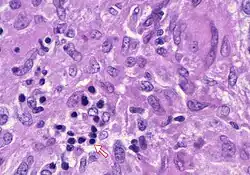

In pathology, a Councilman body, also known as a Councilman hyaline body or apoptotic body, is an eosinophilic globule of apoptotic hepatocyte cell fragments. Ultimately, the fragments are taken up by macrophages or adjacent parenchymal cells.[1] They are found in the liver of individuals suffering from acute viral hepatitis, yellow fever, and other viral syndromes.[2]

With a bright field microscope, Councilman described typical, discrete, necrotic lesions in human hepatic cells of those infected with yellow fever.[9] He noted that the bodies appeared to be red in hematoxylin and eosin-stained sections of hepatic tissue, while being circumscribed, varying in size, round or irregular shape, and having numerous vacuoles of different sizes.